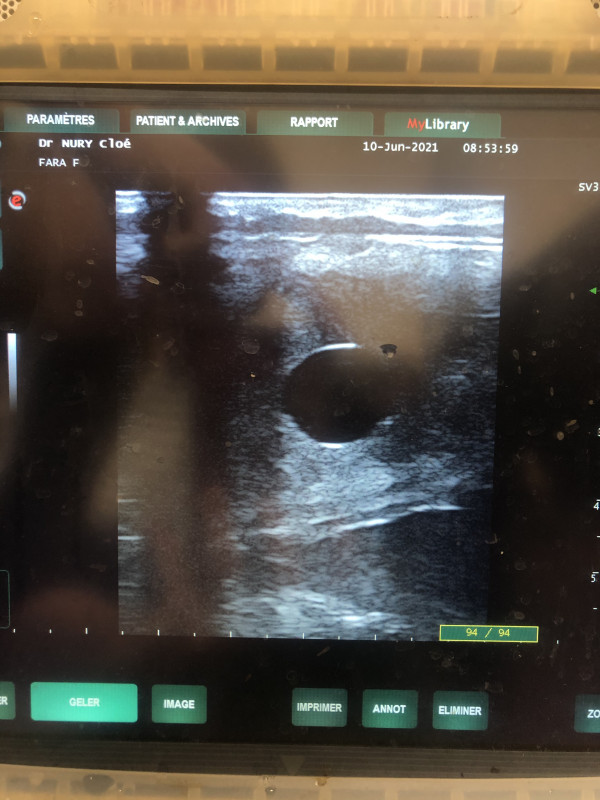

Arwine est pleine d'Arlequin de Mormal

Trop heureuse !!

Plus qu'à aller la chercher maintenant et attendre l'echo de confirmation

Tiana est pleine d'Ambre d'elincourt, prochaine écho semaine prochaine mais on y croit !!!